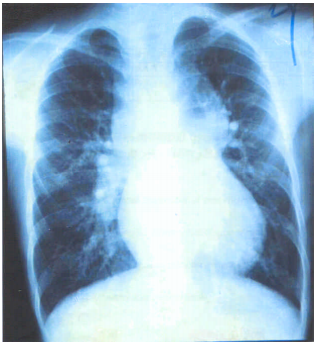

32 5 歲男孩主訴運動時嘴唇稍發紺(cyanosis),且較正常人喘。於左胸前可聽到第 2-3 度心雜音。其胸部 X 光檢查如圖所示。心導管檢查發現兩心房、兩心室、肺動脈及主動脈的血氧濃度均約為 89%。下 列何者為最可能的診斷? (A) 矯正型大血管轉位(corrected transposition of great arteries) (B) 大血管轉位合併心室中隔缺損(transposition of great arteries with VSD) (C) 總肺靜脈回流異常(total anomalous pulmonary venous return) (D) 冠狀動靜脈管(coronary arteriovenous fistula)